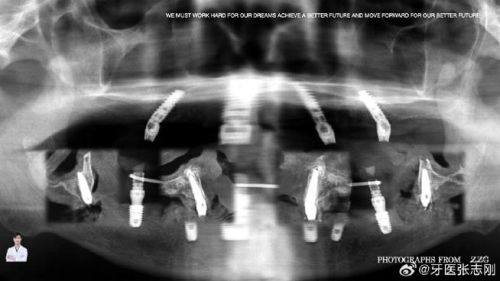

种植牙相关:精通各类种植牙手术,包括ALL-on-4全口即刻负重种植技术,可适配多种进口种植体,同时开展种植牙口腔软组织的美容修复,帮助患者修复缺牙的外观与功能。

拥有二十余年的口腔临床种植经验,熟练掌握ALL-on-4全口即刻负重种植技术,可通过少量种植体完成全口牙修复,有效缩短患者的治疗周期。